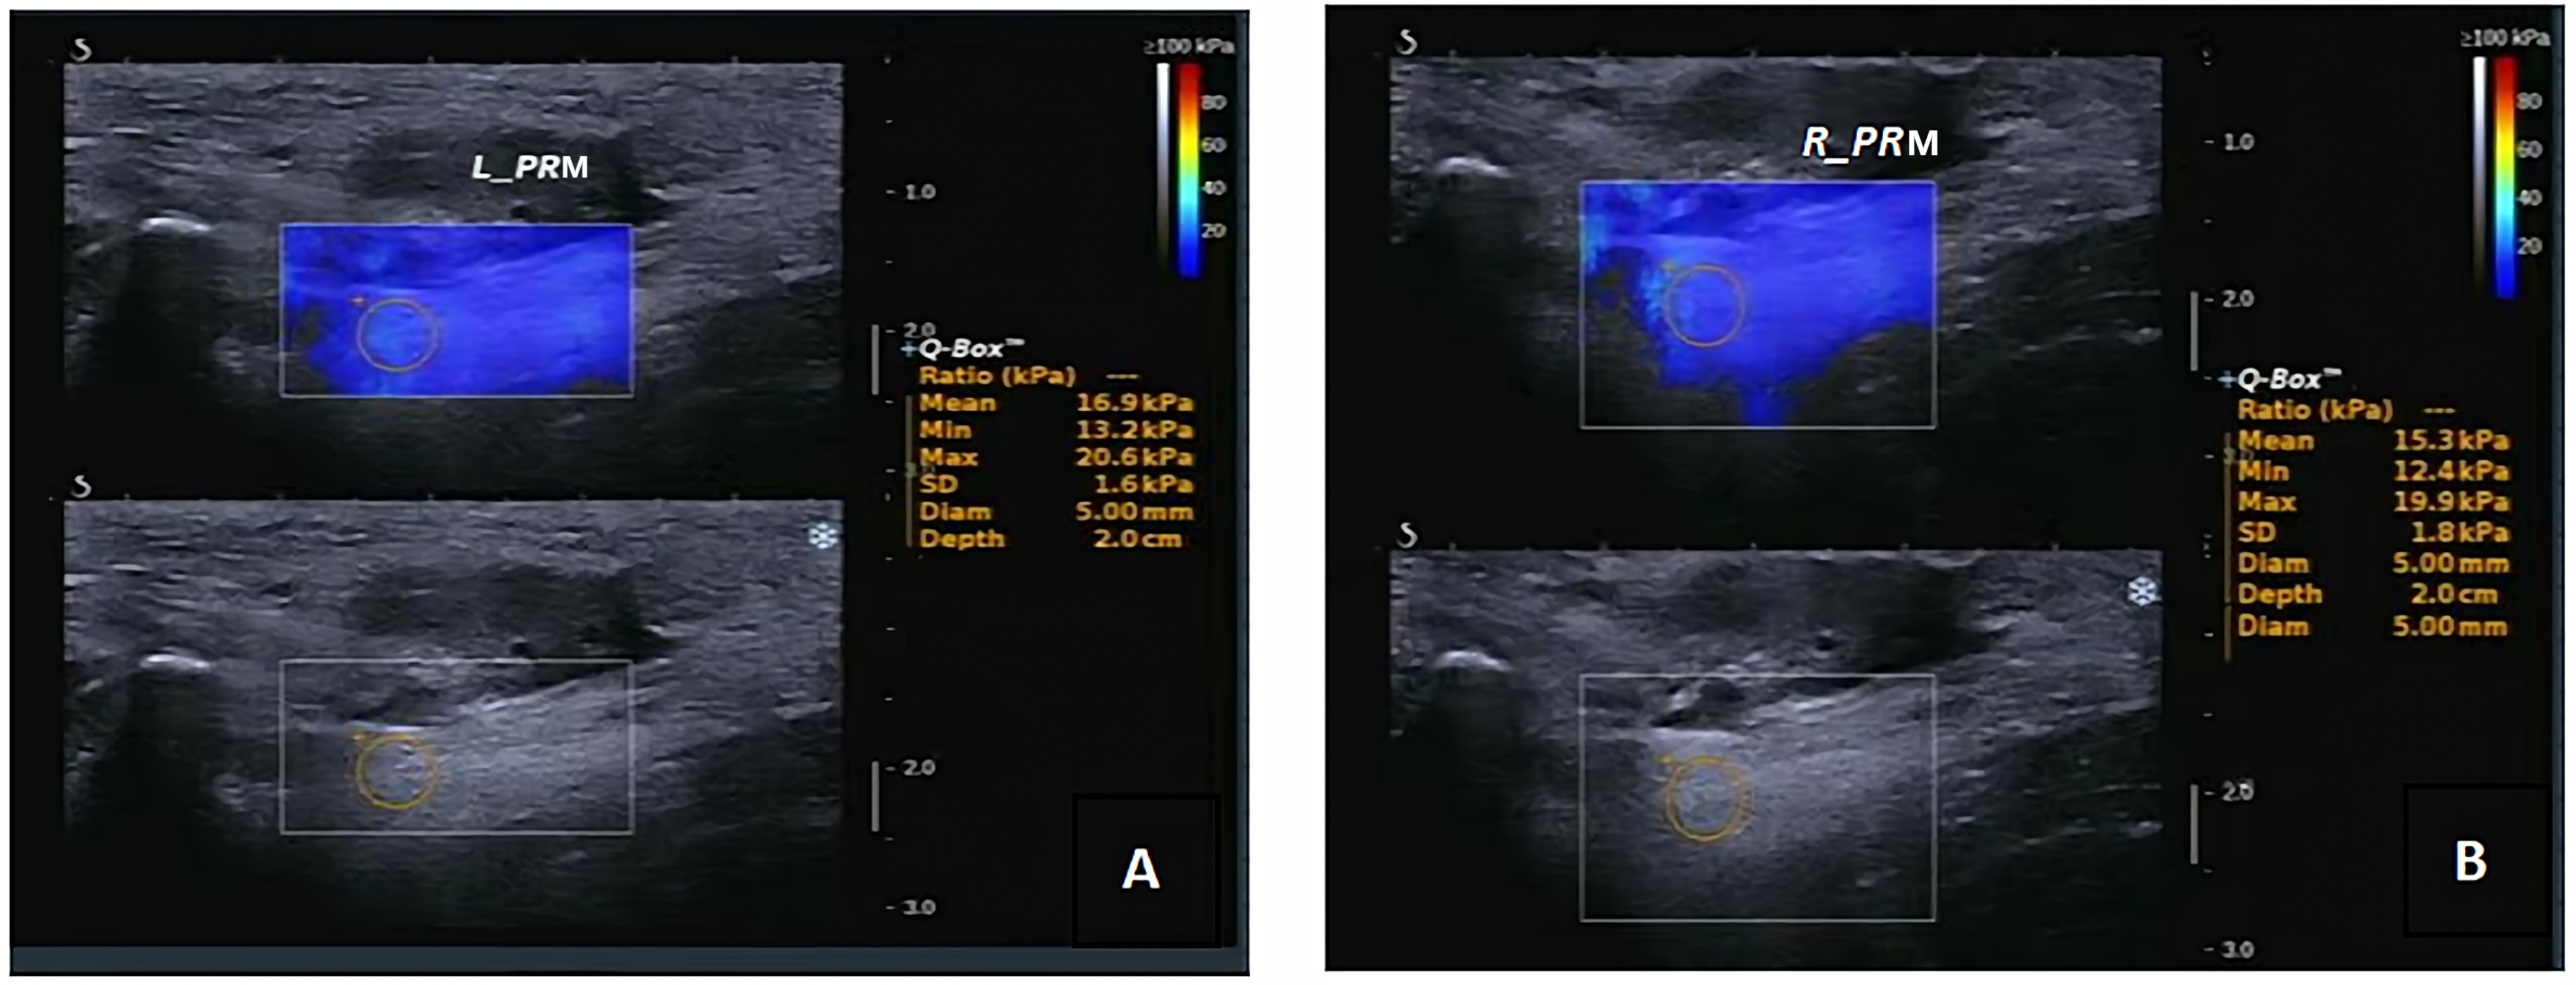

After bladder emptying, subjects assumed a lithotomy position. To minimize the impact of posture on examination results, consistent angles of hip abduction and knee flexion were maintained throughout the procedure. The examinations were conducted using a SuperSonic Aixplorer ultrasound diagnostic instrument (SuperSonic Imagine Company, Aix-en-Provence, Franch) with a 4–15 MHz high-frequency linear array probe. The probe, placed in the median sagittal plane of the perineum directly above the anus, was rotated approximately 10°–20° clockwise and counterclockwise to locate the left and right PRM. Once the two-dimensional ultrasound displayed complete bilateral PRM muscle bundles, the RT-SWE program was initiated. Young’s modulus for elastography was set to 180 kPa, and a rectangular sampling frame was used to cover the PRM maximally [14]. The region of interest (ROI) for measuring PRM’s elastic modulus was a 5.0 mm diameter circle. Tissue elasticity was expressed in kilopascals (kPa) using color-coded elastography. The mean elasticity (Emean) of PRM was calculated by repeating measurements three times on the anterior part of the bilateral PRM, as depicted in Fig. 1.

Fig. 1.

Real-time shear wave elastography was used for Measurement of the anterior elastic modulus of both the left and right PRM. (A) left PRM Emean; 16.9 kPa, (B) right PRM Emean: 15.3 kPa. PRM, puborectalis muscle; Emean, mean elasticity; kPa; kilopascal.